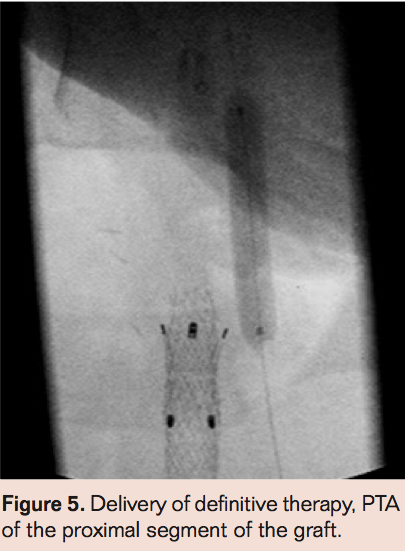

- Laser thrombectomy at 1 mm/sec. with the 2.3 mm probe (Figures 4-9)

- Repeat angiography, and if there is no obvious thrombus proceed to definitive therapy. If there is no flow, then perform angiography via side hole perfusion catheter placed across the occlusion to determine residual thrombus. Patients with residual thrombus are treated with TNK infusion via infusion catheter at 0.5 mg/hr. Repeat angiography at 3 hours to assess patency. If necessary, perform prolonged lytic infusion followed by definitive therapy.